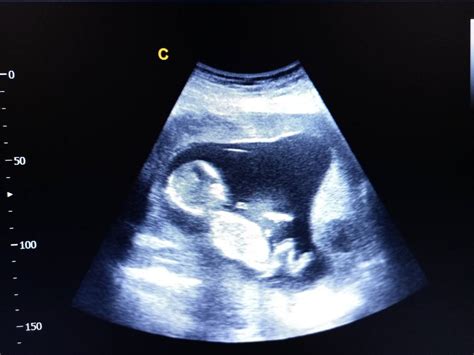

Cu cateva saptamani inainte de data estimata a sarcinii, medicul iti va palpa abdomenul pentru a localiza capul, spatele si fesele copilului. Daca exista vreo suspiciune ca bebelusul se afla in prezentatie pelviana, medicul obstetrician va efectua o ecografie pentru a confirma pozitia.

Este indicat sa se incerce schimbarea pozitiei copilului intre saptamanile 32 si 37 de sarcina. Este un termen medical sofisticat care inseamna repozitionarea corecta a copilului in uter. Este o manevra nonchirurgicala, in care medicul obstetrician va impinge usor la nivelul abdomenului inferior pentru a intoarce copilul cu capul in jos. Pentru efectuarea acestei proceduri, ti se va administra un tratament care produce relaxarea uterul si se va efectua initial o ecografie pentru evaluarea pozitiei copilului, localizarii placentei si a cantitatii de lichid amniotic. In timpul manevrei, bataile cordului copilului vor fi atent monitorizate astfel incat daca apare vreo problema, medicul sa poata sa se opreasca imediat.